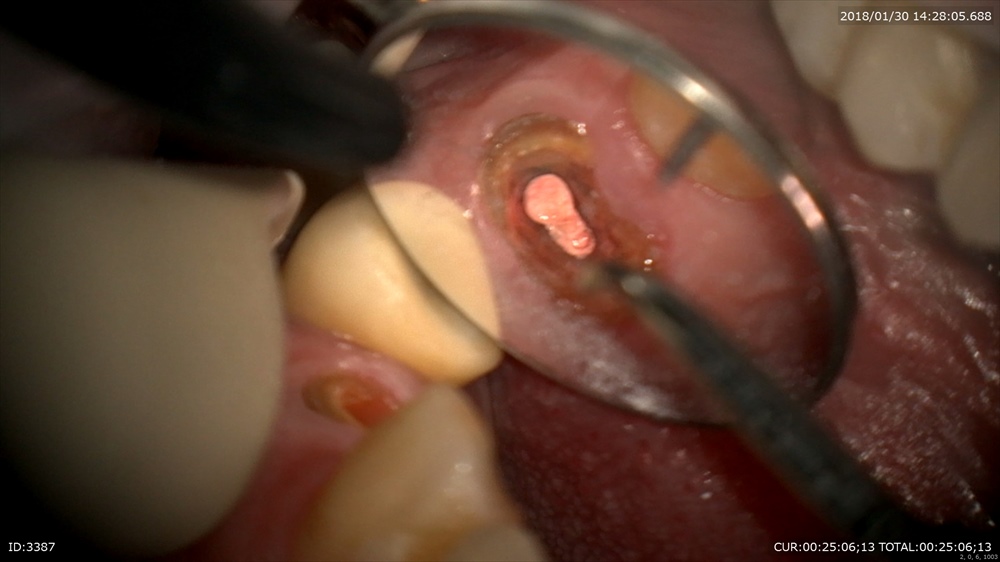

精密根管治療

根管充填